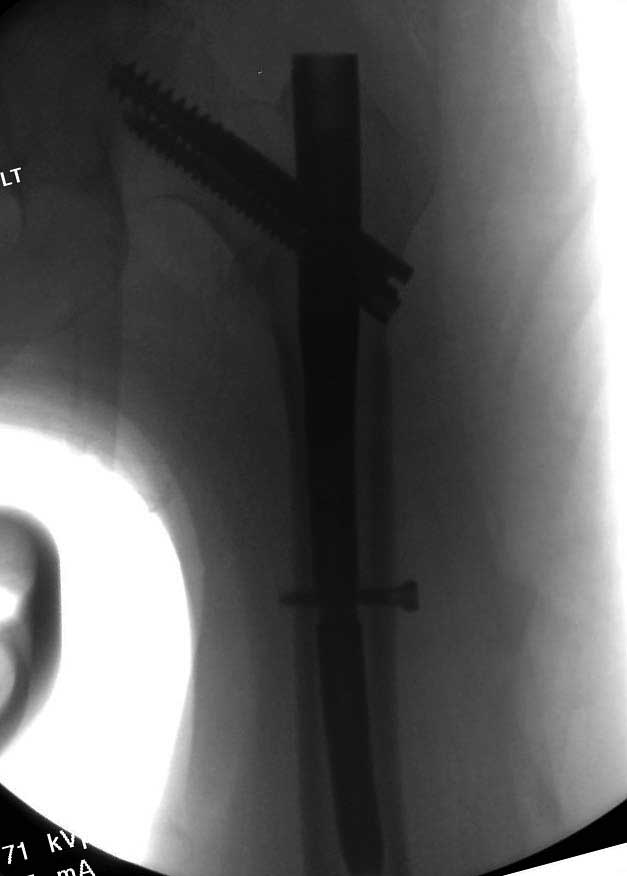

Такие “чужие осложнения” встречаются у всех и представляю банальный случай, который шаг за шагом показано как перерос в более сложный процесс... Больная 70 лет, множественные ко-морбидности, чрезвертельный перелом первоначально фиксирован Гамма 3. Осложнение в течение 6 недель, ревизия тотальной артропластикой и во время установки ножки обнаружена трещина диафиза (17), из малого доступа фиксация алло-графтом.

Обычно после чрезвертельных переломов, за исключением молодых, у пожилых остается нестабильность при движении. Часто падают и после 3х мес. в результате падения обнаружен перипротезный перелом (22-23), который зафиксирован Синтез пластиной.

Повторно поступает после двух с половиной лет, где обнаруживается перелом на второй стороне. Немного сложно, но для фиксации выбрали Antegrade InterTan Smith Nephew Nail и с момента фиксации более 3х мес.